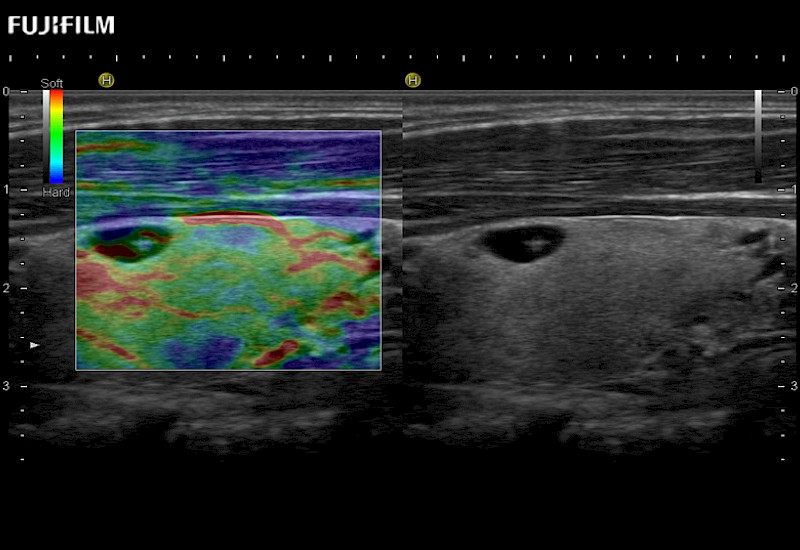

For precise surgical oncology ultrasound imaging, Fujifilm Healthcare offers premium level solutions that include:

Extraordinary high-resolution digital imaging

Multi-Parametric imaging modalities

Our dedication to Surgical Oncology allows us to offer superior image quality, outstanding system reliability and intuitive use of cutting edge technology.

The ARIETTA 750 incorporates all of the proven technologies and functions that medical professionals have come to expect from Fujifilm Healthcare.

ARIETTA 750 is the definitive diagnostic ultrasound solution for any clinical setting - Private Office, Imaging Center, or Hospital. The ARIETTA platform provides the ultimate in clinical performance with its state-of-the-art features and large user-friendly display.

The ARIETTA 650 DI combines trusted Fujifilm Healthcare technologies and features tailored for surgical oncology.

Designed to meet the demands of surgeons, the ARIETTA 650 DI offers precise guidance. Its advanced capabilities and large, intuitive display offer accurate and efficient care in operating rooms and specialized surgical settings.

Fujifilm Healthcare continues to listen to the experts, our neurosurgeons, by developing an ultrasound system specifically designed for the Operating Room.

Guidance is the fundamental purpose for all of our surgical ultrasound technology. Fujifilm Healthcare is committed to designing tools that help neurosurgeons navigate inside the human body and provide the necessary information to immediately make critical surgical decisions.

With the ARIETTA Precision the next level of surgical ultrasound is here.